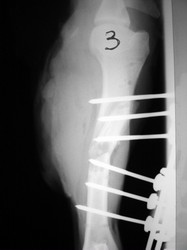

Fijación Externa

Fijación externa en IVOT

PRÁCTICAS CURSO DE FIJACIÓN EXTERNA PERFECCIONAMIENTO.

Húmero.